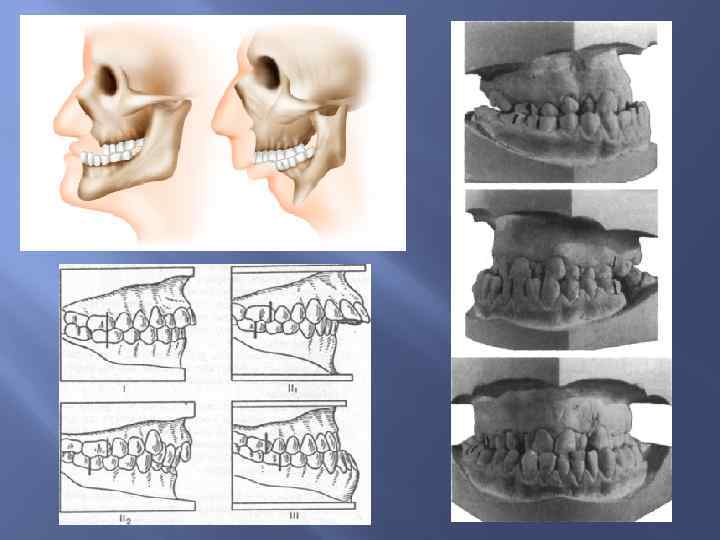

Развитие слюнных желез Околоушная слюнная железа развивается из эпителия ротовой полости, т. е. эктодермального происхождения. Подчелюстная и подъязычная слюнные железы развиваются из эпителия глотки, т. е. энтодермального происхождения. Развитие зубов На 7 -й неделе эмбрионального периода развития эктодерма верхних и нижних челюстных отростков образует зубные пластинки, погружающиеся в мезенхиму челюстных отростков. Из этих пластинок формируются эмалевые органы, клетки которых — адамантобласты образуют эмаль. Мезенхима образует зубной сосочек, адамантобласты которого образуют дентин, а ментобласты — цемент. ш

Развитие слюнных желез Околоушная слюнная железа развивается из эпителия ротовой полости, т. е. эктодермального происхождения. Подчелюстная и подъязычная слюнные железы развиваются из эпителия глотки, т. е. энтодермального происхождения. Развитие зубов На 7 -й неделе эмбрионального периода развития эктодерма верхних и нижних челюстных отростков образует зубные пластинки, погружающиеся в мезенхиму челюстных отростков. Из этих пластинок формируются эмалевые органы, клетки которых — адамантобласты образуют эмаль. Мезенхима образует зубной сосочек, адамантобласты которого образуют дентин, а ментобласты — цемент. ш

Аномалии развития зубов

Аномалии развития зубов